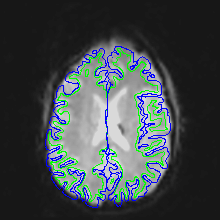

The following images show a T1 image with outlines for the outer boundary of gray matter (blue line) and white matter (green line).

Here are uncorrected EPI images with the same boundaries overlaid.